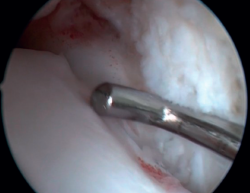

La confirmación del PAT se hará mediante visión directa durante la exploración artroscópica (Figura 4). Esta técnica permite visualizar toda la articulación, evaluar el estado del cartílago articular, los ligamentos, detectar la presencia de adherencias capsulares, sinovitis, engrosamiento sinovial, cuerpos libres, etc. Además, nos permitirá realizar test funcionales para poner de manifiesto posibles inestabilidades asociadas o valorar cómo se pinzan las partes blandas causantes de dolor. La presencia de lesiones del LTFA es, en nuestra experiencia, muy frecuente.

Figura 4. Pinzamiento anterolateral de partes blandas en un paciente con lesión concomitante del ligamento talofibular anterior, al que se le hizo una reparación artroscópica asociada a la resección del pinzamiento.